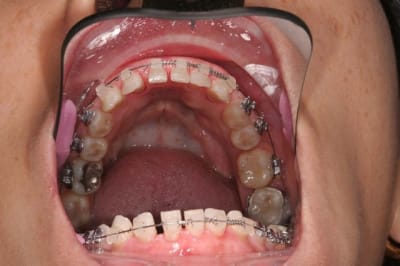

entre temps il y a de l'odf pr réaligner les incisives du bas(diastèmes se modifient d'après la patiente), à la demande de la patiente et parceque la fracture de 11 au bout de tant d'années me questionne...

la CCM est en prov de luxe

(ça tombait bien,la teinte est moyenne,bien qu'elle passe mieux en bouche que sur la photo:le flash?)

la patiente part en vacances

je la referai en septembre

avec ou sans chir?...

il y a eu remodelage naturel(comme quoi entre la theorie et la clinique): peut on le considérer comme suffisant?

autre question:"les incisives du bas"

la patiente a entamé son traitement odf pr une demande esthetique(marre des diastème)

pr des raisons fonctionnelles aussi,cela ns paraissait une bonne idée

elle a une microdontie relative de ces insicives qui st maintenant redressées, alignées avec des diastèmes equidistants

et maintenant....

que feriez vous?

on comprend mieux la microdontie relative

les diastemes te genent? tu as peur de la recidive apres l'ortho?